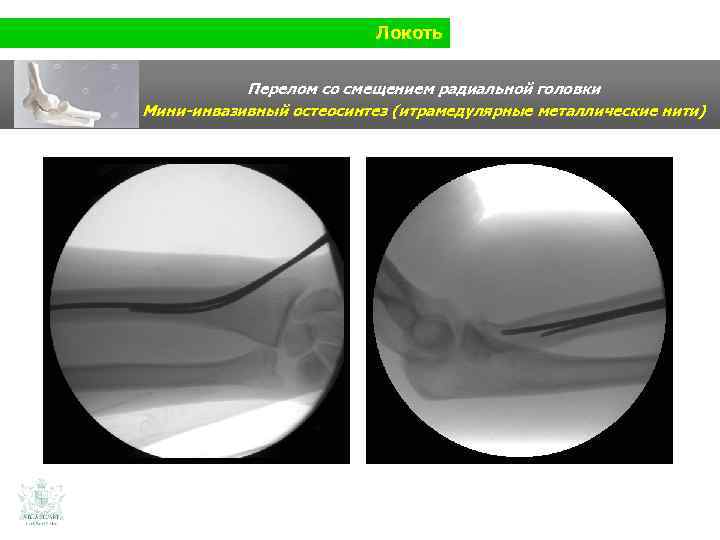

Локоть Перелом со смещением радиальной головки Мини-инвазивный остеосинтез (итрамедулярные металлические нити)